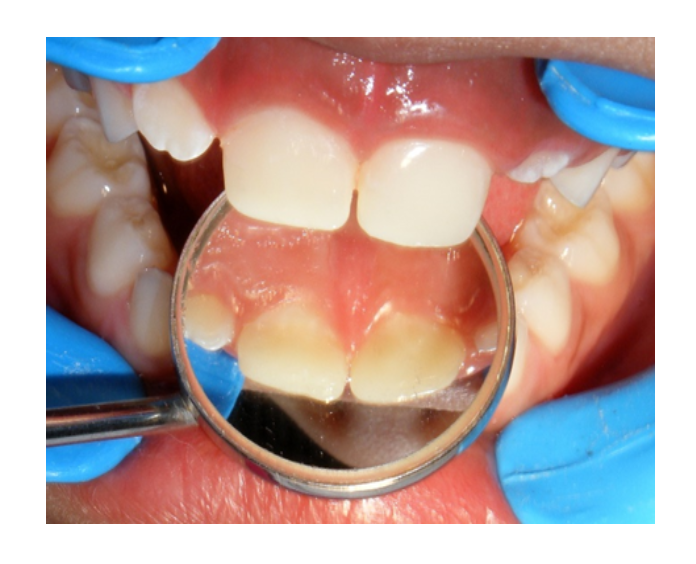

Odontología

infantil